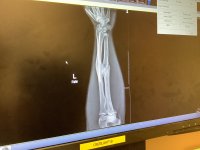

I was thinking. Maybe I should share a little more detail about the injury and the first surgery. Maybe it will lend some perspective , because right about here in the journey..... The pain was becoming too much! I had pushed my hand through freezing cold while soaking wet; through a thousands of miles of riding by this point and it was starting to take a toll !IMG_0874.jpegIMG_0873.jpegIMG_0781.jpeg